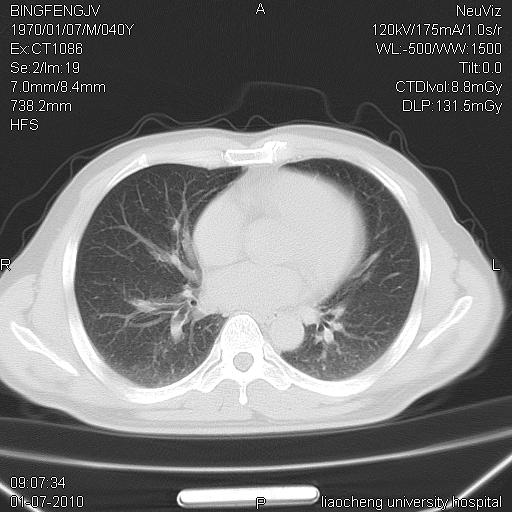

标题: CT23764B:男 40 肺部CT [打印本页]

标题: CT23764B:男 40 肺部CT

治疗2周后

炎症性病灶,继发性改变。

考虑左肺上叶近胸膜下炎症并肺气囊形成。

炎症,大部吸收。